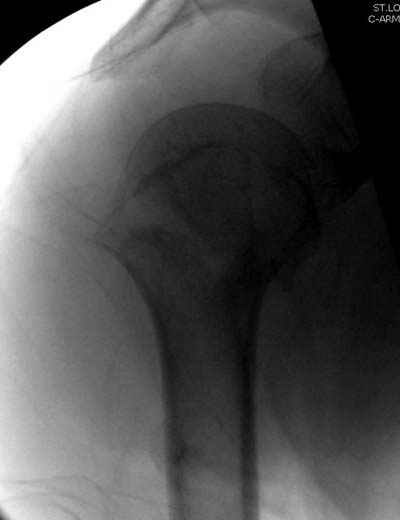

Здравствуй Женя. Во первых спицы, вводимые в головку плеча ретроградно, никогда не имели V-образную форму, если говорить о методике моей операции ЦИТО. Чтобы легче было запомнить Y-образную форму, вспомни крепление новогодних елочных шаров - очень демонстративно. Кроме того если ты внимательно посмотришь, то увидишь, что вся конструкция имеет некоторую кривизну по плокскости, величину, которой ты можешь задать сам. Сначала мы проводим проксимальный пучок, а в момент пересечения линии перелома мы

ротируем спицу таким образом, чтобы дистальный изгиб прямо противодействовал смещающим силам - поврот за ушко под контролем ЭОПа. Дистальный пучок стараемся провести так, чтобы его бранши расклинились и прошли по обе стороны предыдущего пучка, что создает дополнительное напряжение на

протяжении контакта. Для оценки правильности проведения спиц очень важно, чтобы ЭОП стоял строго перпендикулярно плоскости сустава, в противном случае - в рентгене есть эффект отбрасывания тени - прохождение косого луча дает удлиненное изображение спиыц и создается впечатление, что спица стоит уже в субхондральном слое. На первых операциях у нас было довольно частое несовпадение длины контрольной спицы и мы провизорно добавляли от 0,5 до 1,0 см уже на фиксирующем пучке. Входные отверстия лучше располагать по наружной и передней поверхности плеча на расстоянии не менее 2-х диаметров головки.

Такой выбор входных отверстий обусловлен прямой возможностью попадания в малый и большой бугорки за счет изгиба спиц по длине и отражения из от внутреннего кортикала проксимальнее точки введения. Поскольку анатомически бугорки не составляют артикулирующую поверхность, то некоторое выстояние спиц только усилит стабильность. Входное отверстие мы используем 6 мм в диаметре, для эффективного раскрытия петли-пружины. Спицы перед проведением

проверяем на достаточную эластичность и упругоустойчивость, мягкие спицы отбраковываем. В данном примере создалось впечатление, что одна бранша V-спицы скользнула по картикалу снаружи? Все это безболезненно можно переделать, расширив теже отверстия, изогнув спицы, повернув их в разные стороны и добавив еще пучки Y-ОБРАЗНЫХ, а не V-образных (эти пучки выталкивает, особенно если они прямые - пружина работает в обе стороны).